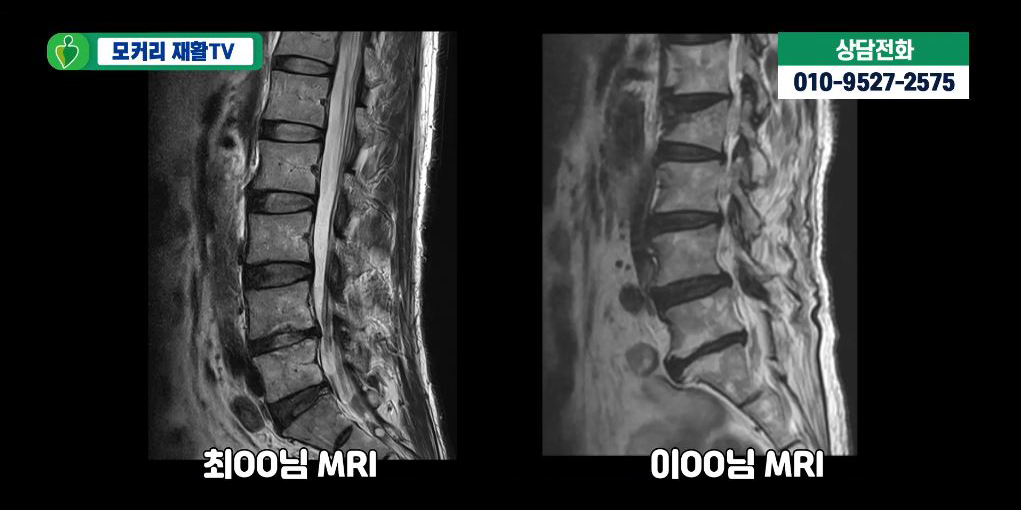

이 글은 경추 MRI 결과지를 받아든 환자 입장에서

반드시 짚고 넘어가야 할 포인트를 정리한 글입니다.

의학 교과서가 아니라,

판단에 필요한 최소한의 기준에 집중하겠습니다.